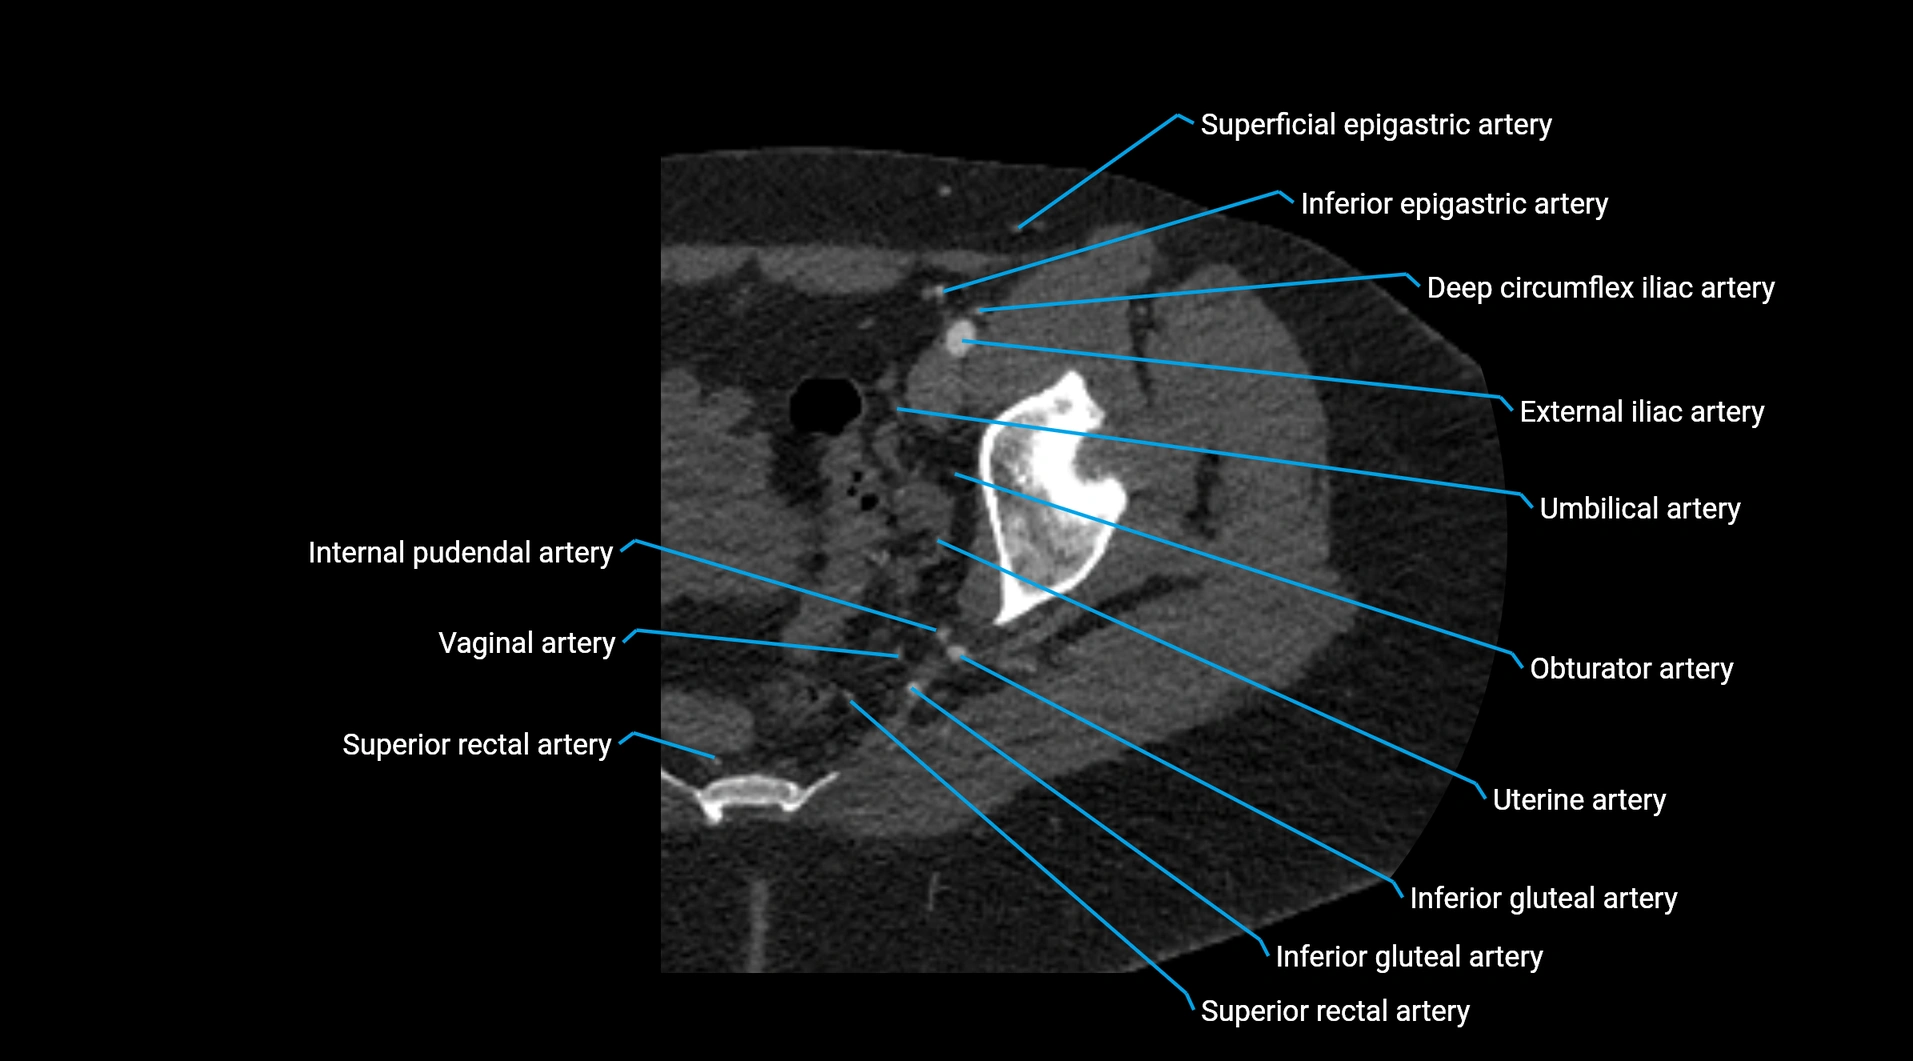

CT images

image